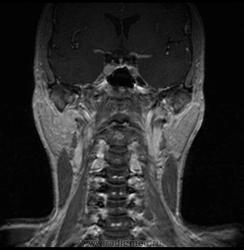

06.06.2011 МРТ - головы и шеи.

Пацентка 36 лет, с жалобами на припухлось в околоушной области справа.

В глубокой доле  правой околоушной железы  на фоне неизмененной паренхимы зона  гетерогенного по Т2, гипоинтенсивного по Т1  с единичными гиперинтенсивными включениями.При контрастировании- накопление контраста диффузное неоднородное и по периферии.Рискну предположить злокачественное образование ( аденокарцинома) с низкой степенью злокачественности( есть капсула, экспансивный рост).Сильно не расстреливайте.

Проблема в том, что перед челюстно-лицевым хирургом стоит распространенность любого объемного процесса, в данном случае все упирается в возмможную травму лицевого нерва и конечно же с дальнейшим его парезом, а ведь женщина  еще молодая. Образование имеет тонкостенную оболочку, по структуре неоднородно, с наличием кальцината, при этом МР-сигнал от окружающих анатомических структур(как костных так и мышечных) не изменен, т.е. об инфильтративном росте речи не идет, в какой то степени доброкачественное. В конкретном случае лицевой нерв с ретромандибулярной веной просто несколько оттеснен.

По гистологии аденома околоушной слюнной железы, но после удаления пока сохраняется парез лицевой мускулатуры, возможно временный.